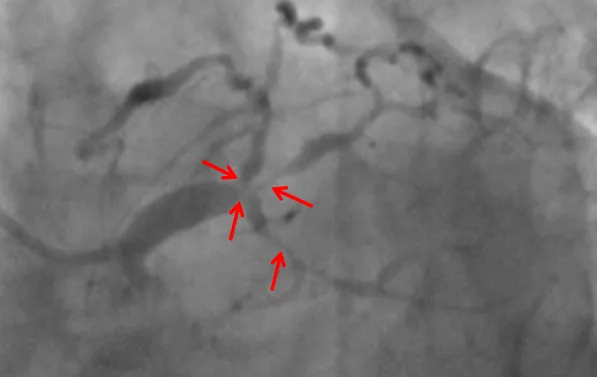

近日,皇冠足球投注网 (简称皇冠足球网 )心血管内科联合重症医学科、心胸外科等科室,在ECMO器械辅助下,为一名复杂高危冠脉病变患者进行了精准冠脉介入治疗,开通病变冠脉血管。目前患者已康复出院。该项技术的开展,标志皇冠足球投注网 对高危复杂患者治疗技术又迈上一个新台阶。患者“心悬一线”辗转多家医院就医无果据了解,69岁的张先生(化名)一年来总是感觉胸口闷胀不适,尤其是上楼、快步...